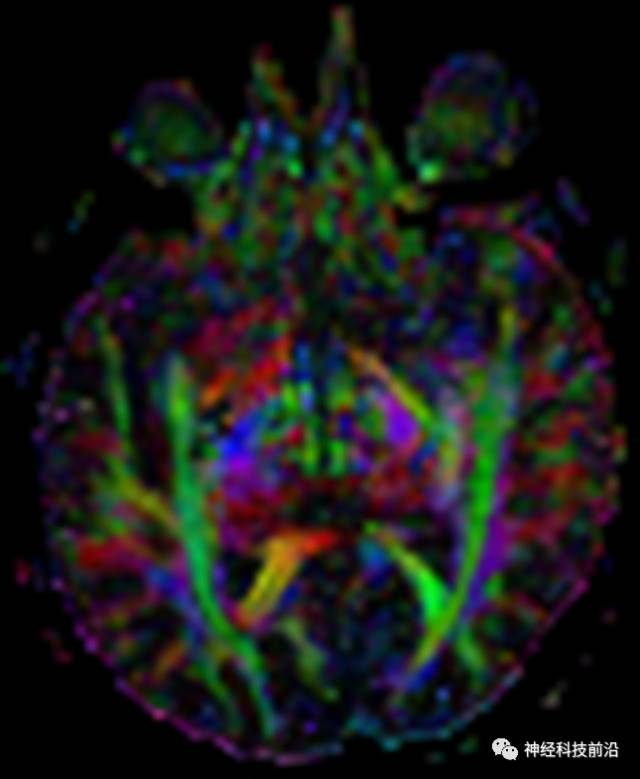

DTI原始图像与T1融合图像